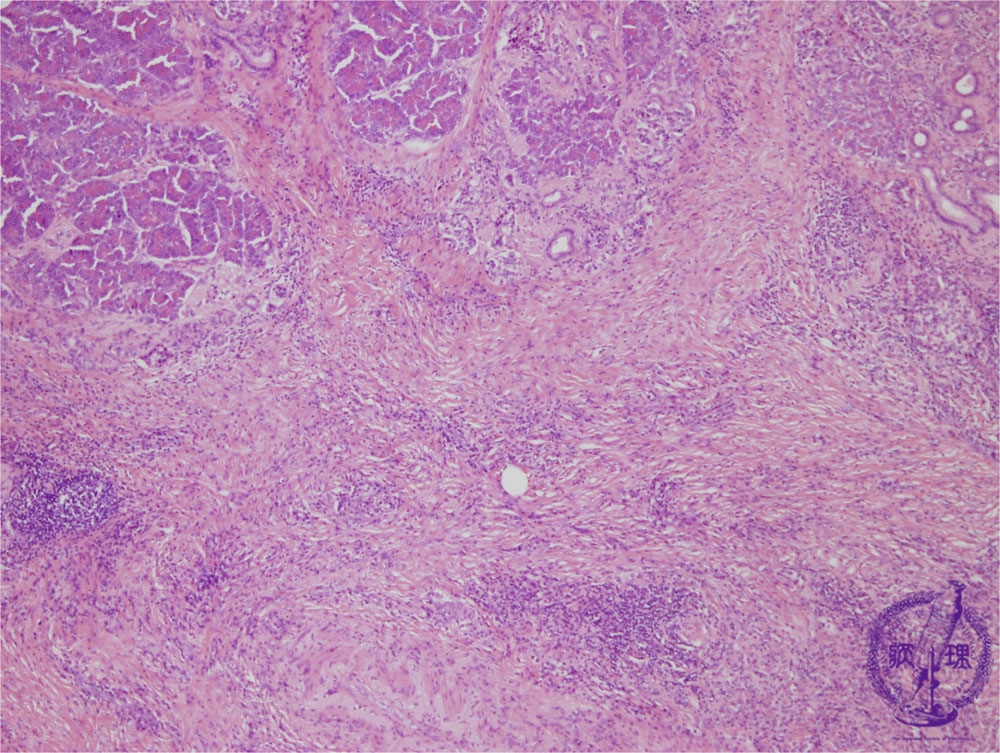

- (5)Chronic pancreatitis

Microscopic image(HE stain, low power): Advanced fibrosis is seen within the pancreatic parenchyma and interlobular spaces. Lymphoid follicles are seen forming amongst the fibrosis (arrows).